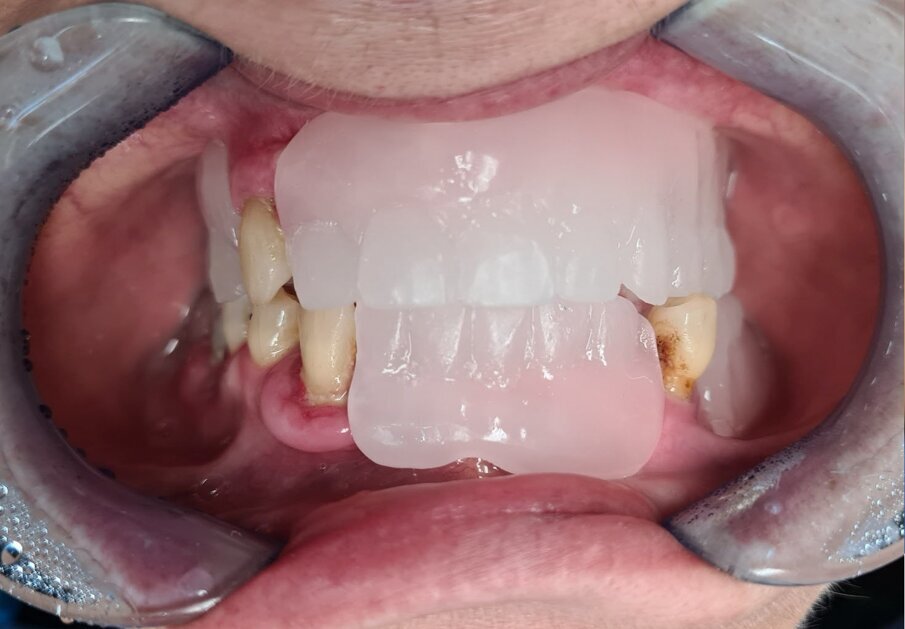

Paziente donna di ottant’anni, presenta uno stato di salute ottimale, non assume farmaci. Dal punto di vista odontoiatrico chiede una riabilitazione delle due arcate con dei denti fissi perché le attuali protesi removibili con ganci le stanno creando ormai da troppi anni un grande disagio. Come dalla ortopantomografia possiamo evidenziare uno stato ormai precario degli elementi rimasti (Figg. 1-3).

Fig. 1_Caso iniziale senza protesi.